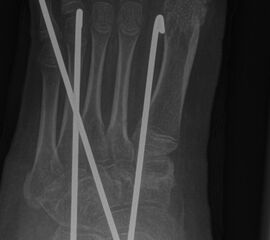

Zusätzlich schränken Wachstumsfugen die Wahl der Osteosynthese ein. Eine die Fuge kreuzende Osteosynthese ist ausschließlich mit Kirschner-Drähten möglich (Abb. 3).

Abb. 3 a-j: Beispiel einer Calcaneusverschiebeosteotomie mit offenen Wachstumsfugen und der entsprechenden Osteosynthese mit Kirschner Drähten. Lokalisation der Osteotomie (a), Lage der Fräse (b-d), Drahtlage mehrere Ansichten (e-h), Heilung der Osteotomie 4 Wochen postoperativ und Entfernung der Drähte (i-j).

Zum Lesen der Bildbeschreibung und zur Vollansicht bitte die Bilder anklicken. Bilder: A. Helmers.

=> Osteosynthese aufgrund offener Fugen eingeschränkt

Wachstumsfugen können, wie bereits oben in der generellen Einschätzung des Verfahrens für Kinder und Jugendliche erwähnt, durch direkte Manipulation mit einer Fräse oder indirekt thermisch geschädigt werden. Eine Osteosynthese, die offene Wachstumsfugen kreuzt, ist ausschließlich mit Kirschner-Drähten oder alternativ durch externe Tapezügel möglich. Implantierte Kirschner-Drähte können ohne eine weitere Narkose im Rahmen der Sprechstunde bei verheilter Osteotomie gezogen werden. Die Anwendung von externen Tapezügeln zur Stabilisierung von minimalinvasiven Osteotomien kann bei Kindern ohne Einschränkung durchgeführt werden (siehe Abb. 4 und Abb. 12). Bei sehr jungen Kindern sollten die Tapezügel allerdings nicht zu häufig gewechselt werden, da jeder Verbands- und Tapewechsel Stress für sie bedeutet.